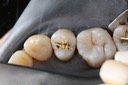

Kyle Chock #15 pre-op